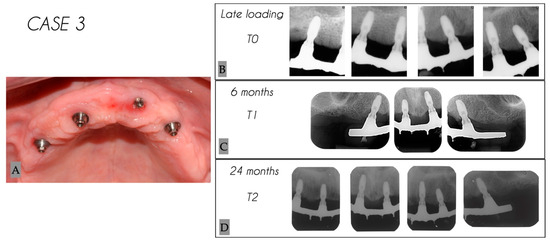

| 3 | Male | 68 | Maxilla | 4 |

| Case No. | Tooth No. | Initial MBL (mm) | MBL 6 Months (mm) | MBL 24 Months (mm) | KM 6 Months (mm) | KM 24 Months (mm) |

|---|---|---|---|---|---|---|

| 3 | 24 | 1.43 | 1.51 | 1.82 | 6 | 6 |

| 3 | 22 | 0.38 | 0.6 | 0.97 | 3 | 3 |

| 3 | 12 | 1.57 | 1.86 | 2.23 | 3 | 3 |

| 3 | 15 | 1.81 | 1.89 | 1.99 | 4 | 4 |

| Mean | 1.30 | 1.47 | 1.75 | 4.0 | 4.0 | |